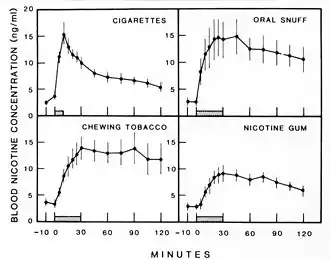

Physiology

The active substances in tobacco, especially cigarettes, are administered by burning the leaves and inhaling the vaporized gas that results. This quickly and effectively delivers substances into the bloodstream by absorption through the alveoli in the lungs. The lungs contain some 300 million alveoli, which amounts to a surface area of over 70 m2 (about the size of a tennis court). This method is not completely efficient as not all of the smoke will be inhaled, and some amount of the active substances will be lost in the process of combustion, pyrolysis.[5] Pipe and Cigar smoke are not inhaled because of their high alkalinity, which is irritating to the trachea and lungs. However, because of its higher alkalinity (pH 8.5) compared to cigarette smoke (pH 5.3), non-ionized nicotine is more readily absorbed through the mucous membranes in the mouth.[53] Nicotine absorption from cigar and pipe, however, is much less than that from cigarette smoke.[54] Nicotine and cocaine activate similar patterns of neurons, which supports the existence of common substrates among these drugs.[55]

The absorbed nicotine mimics nicotinic acetylcholine, which when bound to nicotinic acetylcholine receptors prevents the reuptake of acetylcholine thereby increasing that neurotransmitter in those areas of the body.[56] These nicotinic acetylcholine receptors are located in the central nervous system and at the nerve-muscle junction of skeletal muscles; whose activity increases heart rate, alertness,[6] and faster reaction times.[7] Nicotine acetylcholine stimulation is not directly addictive. However, since dopamine-releasing neurons are abundant on nicotine receptors, dopamine is released; and, in the nucleus accumbens, dopamine is associated with motivation causing reinforcing behavior.[57] Dopamine increase, in the prefrontal cortex, may also increase working memory.[58]

When tobacco is smoked, most of the nicotine is pyrolyzed. However, a dose sufficient to cause mild somatic dependency and mild to strong psychological dependency remains. There is also a formation of harmane (an MAO inhibitor) from the acetaldehyde in tobacco smoke. This may play a role in nicotine addiction by facilitating a dopamine release in the nucleus accumbens as a response to nicotine stimuli.[59] Using rat studies, withdrawal after repeated exposure to nicotine results in less responsive nucleus accumbens cells, which produce dopamine responsible for reinforcement.[60]